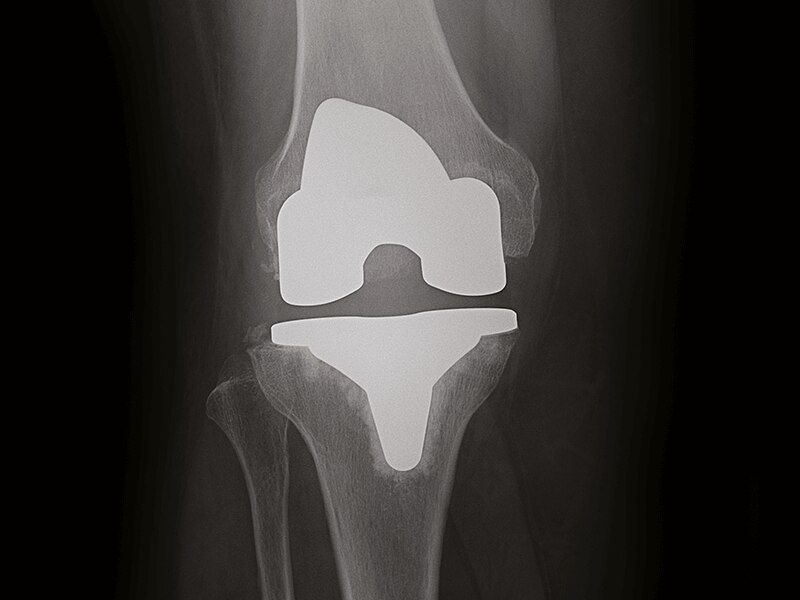

Excellent handling of metal implants

Clear bone-metal interface without halo artifact